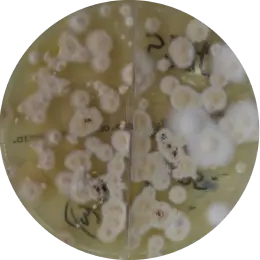

Trichophyton tonsurans

Trichophyton spp